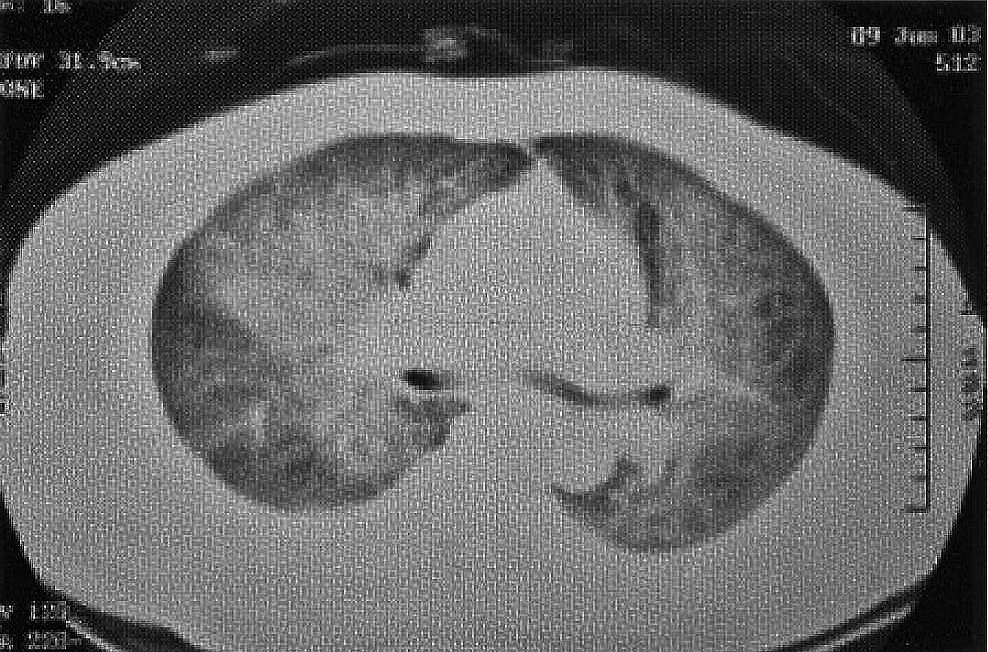

She was treated with intravenous cefotaxime and oral levofloxacin. Her clinical symptoms of fever, chills and myalgia persisted and started to have mild dyspnoea. Moreover, the blood tests repeated on second day of admission showed deranged clotting profile with prolonged APTT (40.2 seconds) and elevated D-dimer level (8 times of normal upper limit), lymphocyte dropped from 1.3 to 1.0 x 109/L. The stool, throat and nasal swabs for SARS coronavirus (CoV) reverse-transcription polymerase chain reaction (RT-PCR) were negative, and IgG-CoV titre sent on 8 June 03 was < 40. In view of the deteriorating clinical and haematological pictures, she was transferred to our hospital’s SARS triage ward on 8 June 2003. The patient required 2 litres/min oxygen to maintain SpO2 ~93% for transferral. Physical examination upon arrival revealed multiple mosquito bites and faint maculopapular rash over both lower limbs, bilateral crepitations over her chest and mildly elevated jugular venous pressure. CXR repeated on 8 June 2003 (Figure 2) showed more extensive bilateral alveolar shadowing. Electrocardiogram showed sinus tachycardia without ischaemic change. HRCT thorax (Figure 3) was performed on 9 June 2003, which showed extensive consolidation with air bronchogram and ground glass opacification in all lungs fields, bilateral pleural effusion with right side more than left side. The differential diagnoses at that juncture included SARS, congestive heart failure with elements of pneumonia, pneumonitis and dengue fever.